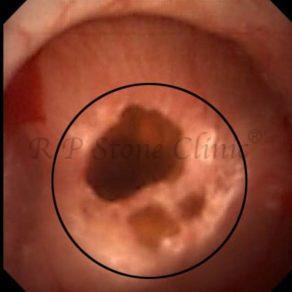

Kidney stone is a solid mass of CRYSTALS. It is the process of crystallization which initiates the formation of kidney stones. This happens in nephrons or units of kidney. Once a small crystal is formed, it can both grow & unite with other crystals leading to the formation of small concretion which eventually forms a stone. Once these large crystals detach from the collecting ducts, the process of stone formation starts in the renal collecting system. A recurrent kidney stone former is advised to know a little bit about something known as Randall’s plaque. Alexander Randall discovered plaques on the renal papillae eight decades back based on examination of 1154 pairs of autopsied Kidneys. He described these renal papillary lesions as cream colored or milk patch areas composed of calcium phosphate & calcium carbonate. These plaques could act as NIDUS for formation of KIDNEY STONE. Calcium Oxalate stone can form on this nidus & then detaches from this plaque to become a free floating stone in the collecting system of kidney

These images are taken as snap shots from the video recording of RIRS Surgery done at our hospital. These are Randall’s Plaques seen with Digital FLEX XC & Digital FLEX XC S. The cream or whitish patches are seen on the tips of RENAL PAPILLAE as seen in images below.

Randall’s Plaques may lead to the formation of Stones.

Those kidney stone patients who have Randall’s Plaques in their kidneys are more likely to form stones again (Recurrent Stones).

Stone Patients in whom Randall’s Plaques are detected at the time of RIRS Surgery should undergo regular ultrasound examination for early detection of stones.

Patients of Stones with Randall’s Plaques in their Kidneys should drink plenty of fluids in addition to Orange Juice & Lemonade.